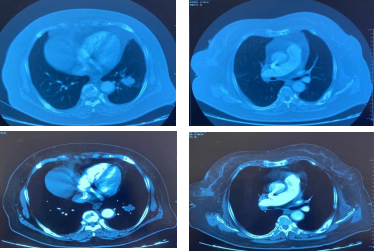

治疗9周期后,病灶增大30%,疗效评估为PD。

靶病灶:左肺病灶增大;

非靶病灶:右肺门较前相仿。

CT检查——治疗9周期后

CT检查——基线

影像学-增强CT检查:治疗2周期后,左肺病灶明显缩小达52.9%,疗效评估为PR。

CT检查——治疗2周期后

治疗6周期后,左肺病灶明显缩小达58.6%,疗效评估为PR。

CT检查——治疗6周期后